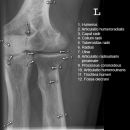

Ellenbogen ventro-dorsal (1. Ebene a.-p.)

Beurteilungskriterien

- Lage der Tuberositas radii zeigt die Stellung des Unterarms: Supination -> Tuberositas zeigt nach medial, Pronation -> Tuberositas zeigt nach lateral

- Physiologische Valgusstellung von 10 – 15°

- Ellenbogengelenkspaltweite: etwa 3mm

- Auftreten, Verschmelzung und Lokalisation der Epiphysenkerne -> Verlagerung? vgl. Anatomie Kids! Viele kindliche Verletzungen sind anhand der Verlagerung der Knochenkerne differenzierbar! Evtl. Vergleich mit Gegenseite oder MRT hilfreich.

- Target areas: Kontinuität der Knochenkontur der Fossa olecrani , der Epikondylen und Kondylen, des Olecranons.

Harmonische Darstellung des Radiusköpfchens? Impressionen? Stufe? Verdichtungen, Fissur? Knickbildung im leicht geschwungenen Radiuskopf-/Hals-Übergangs?

Cave: 50% der Radiusköpfchenfraktur sind nicht disloziert und u.U. nicht nachweisbar -> bei klinischem Verdacht ist ein positives Fettpolsterzeichen in der seitlichen Aufnahme nahezu beweisend! -> Greenspan-Aufnahme, evtl. CT oder MRT!

- Erhaltene Radius-Kapitulum-Achse? Versatz -> Luxation?

- Täuschungsmöglichkeiten: Persistierende Apophysen an Epikondylus medialis, Olecranonspitze, medialem Trochlearand oder Processus coronoideus

- Umgebende Leitungsbahnen: besonders gefährdet bei stark dislozierten Verletzungen sind der N.ulnaris (verläuft im seiner Knochenrinne durch den distalen mediodorsalen Humerus und die A.brachialis (zusammen mit N.medianus ventral des Gelenks)

- Kids: Baumannscher Winkel: Humeruslängsachse – Gerade durch die Epiphysenfuge des Capitulums ~ 70-75°. Wichtig für die Beurteilung der Repositionskontrolle nach supracondylärer Humerusfraktur